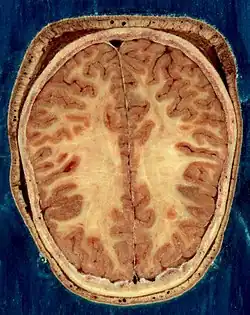

The adult human brain weighs on average about 1.2–1.4 kg (2.6–3.1 lb) which is about 2% of the total body weight,[2][3] with a volume of around 1260 cm3 in men and 1130 cm3 in women.[4] There is substantial individual variation,[4] with the standard reference range for men being 1,180–1,620 g (2.60–3.57 lb)[5] and for women 1,030–1,400 g (2.27–3.09 lb).[6]

The cerebrum, brainstem, cerebellum, and spinal cord are covered by three membranes called meninges. The membranes are the tough dura mater; the middle arachnoid mater and the more delicate inner pia mater. Between the arachnoid mater and the pia mater is the subarachnoid space and subarachnoid cisterns, which contain the cerebrospinal fluid.[11] The outermost membrane of the cerebral cortex is the basement membrane of the pia mater called the glia limitans and is an important part of the blood–brain barrier.[12] In 2023 a fourth meningeal membrane has been proposed known as the subarachnoid lymphatic-like membrane.[13][14] The living brain is very soft, having a gel-like consistency similar to soft tofu.[15] The cortical layers of neurons constitute much of the cerebral grey matter, while the deeper subcortical regions of myelinated axons, make up the white matter.[7] The white matter of the brain makes up about half of the total brain volume.[16]

The outer part of the cerebrum is the cerebral cortex, made up of grey matter arranged in layers. It is 2 to 4 millimetres (0.079 to 0.157 in) thick, and deeply folded to give a convoluted appearance.[21] Beneath the cortex is the cerebral white matter. The largest part of the cerebral cortex is the neocortex, which has six neuronal layers. The rest of the cortex is of allocortex, which has three or four layers.[7]